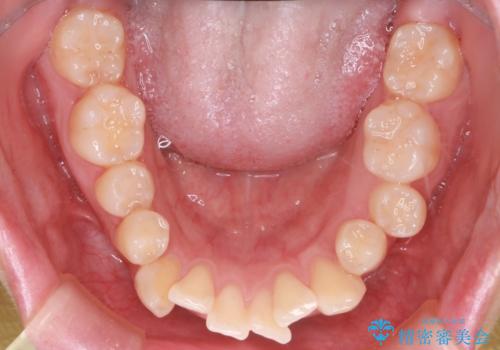

- 前歯の突出が強く、口元が前に出ている印象を改善するため、上下左右の第一小臼歯(4番)を抜歯する矯正治療を計画しました。抜歯により得られたスペースを利用して、前歯を後方へと移動させて整列します。治療には目立ちにくい透明な審美ブラケットとワイヤーを使用し、毎月1回の調整を行いながら徐々に歯を動かし、約2年で口元全体を整える計画としました。

前歯が前に出ているため口元が突出し、唇が閉じにくいなどの悩みを抱えておられました。治療にあたり上下左右の第一小臼歯を抜歯し、十分なスペースを作ることで前歯を効果的に後方へ移動させました。装置には透明で目立ちにくい審美ブラケットを採用し、治療中の審美的ストレスを軽減しました。定期的な調整を通じて無理なく確実に歯列を整え、前歯の突出感を解消。治療後は口元の印象が自然で美しく改善され、患者様には非常にご満足いただけました。